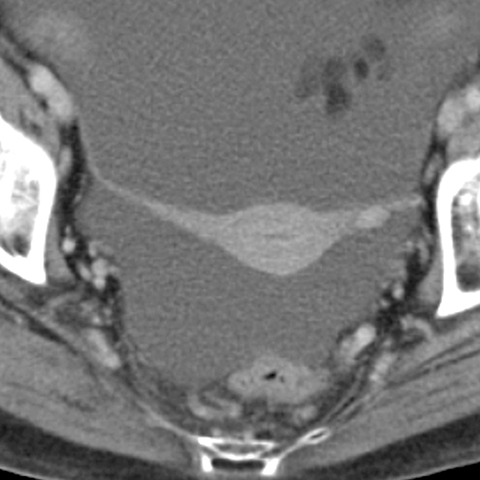

Broad ligaments [3 of 5]